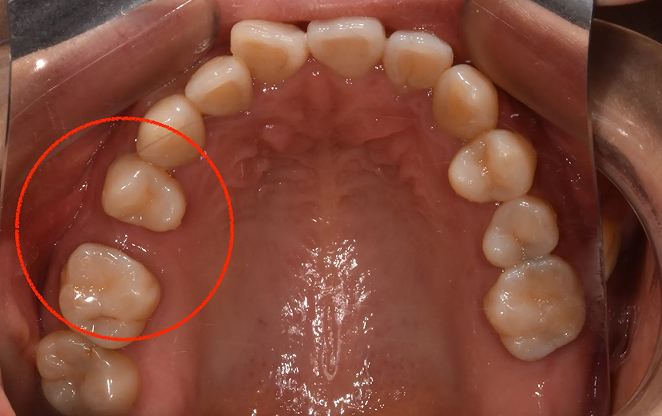

내 치아 그대로 오래쓸 수 있는,

평생 건강한 미소를 위한 비보철 교정

비보철 교정은 치아를 뽑거나 보철물을 사용하지 않고,

내 치아 그대로의 아름다움을 지켜가며 교정하는 방법입니다.

불필요한 보철 없이 치아의 배열을 조정해, 자연스럽고 건강한 치아와

균형 잡힌 미소를 찾아가는 과정입니다. 자연스러움 속에서 완성되는

건강한 미소, 비보철 교정으로 그 여정을 시작하세요.